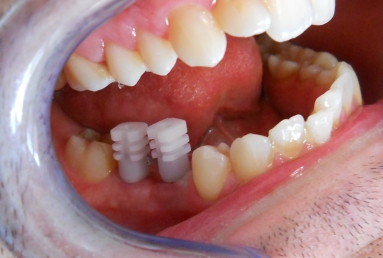

Initial situation: two missing teeth, second lower premolar and first lower molar. two dental implant are integrating in the mandibular bone for 4 months, then, gingival healing caps are applied for 3 weeks. an impression is taken for the dental lab in order to manufacture 2 porcelain fused to metal crowns. they will be screwed directly in the implant body.